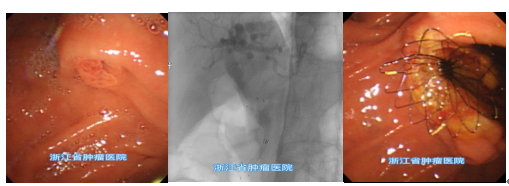

胆道金属支架放置图示